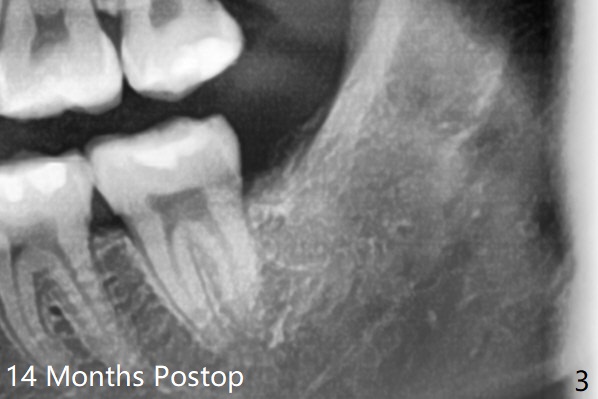

The lower 3rd molar sockets heal in 14 months (Fgi.3).